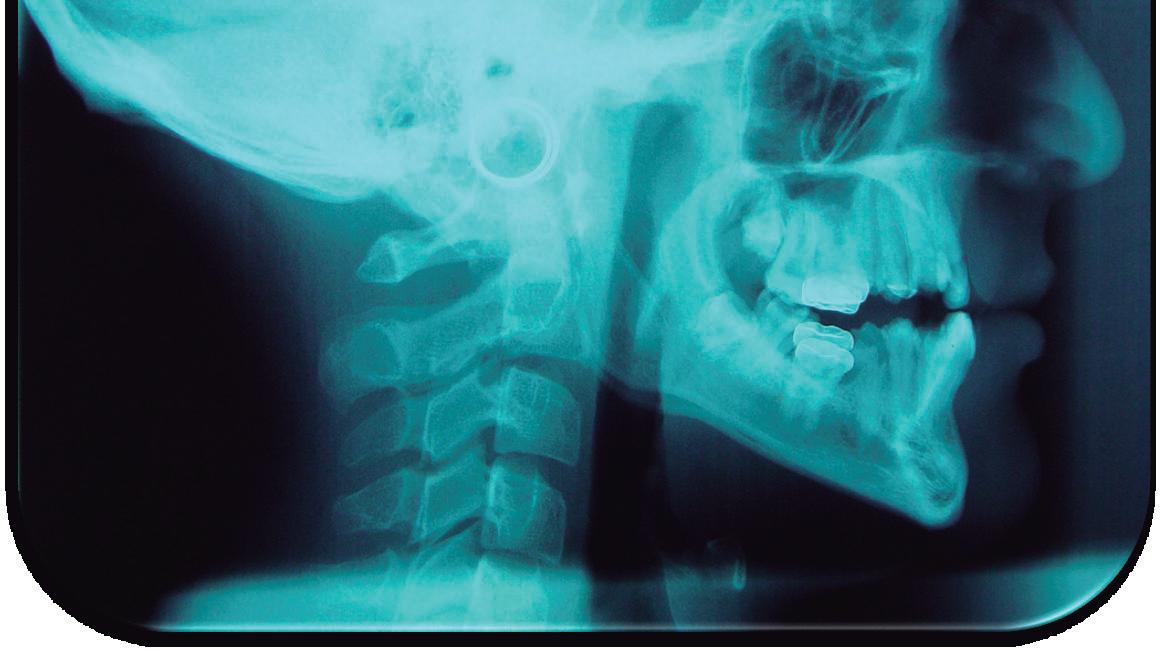

Este manual proporciona información completa y actualizada para profesionales de la odontología acerca de la amelogénesis imperfecta, una enfermedad huérfana que se caracteriza por desórdenes hereditarios que afectan la estructura del esmalte en su calidad y cantidad. Esta patología muchas veces se subdiagnostica en la práctica general, por lo que este manual suministrará una guía que permitirá un diagnóstico certero; además, brindará una clara y comprensible explicación a otros profesionales de la salud, como médicos y nutricionistas, que podrían interactuar con pacientes afectados por esta enfermedad, ya que esta entidad se ha asociado también a factores nutricionales y a enfermedades sistémicas.

A pesar de los recientes avances en la identificación de los defectos moleculares responsables de la aparición de la amelogénesis imperfecta, existe poca información sobre el fenotipo y el genotipo de este

grupo de desórdenes, lo que dificulta el diagnóstico de algunos subtipos clínicos y, por lo tanto, la determinación del programa terapéutico. Describir las características dentales y craneofaciales, así como otras enfermedades asociadas que pueden estar relacionadas con pacientes que padecen amelogénesis imperfecta, proporciona elementos para una adecuada planeación de su tratamiento. La intervención de varios profesionales para remediar los múltiples y severos problemas funcionales y estéticos presentes en esta enfermedad se hace necesaria, así como conocer su etiología genética, con el fin de brindar al paciente una atención integral.